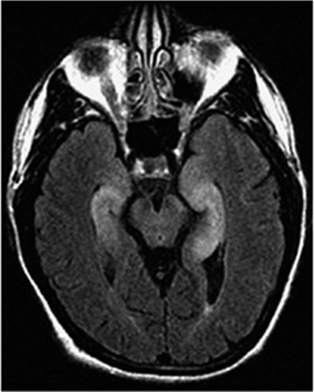

FIGURE 44-2

Fluid-attenuated inversion recovery sequence MRI of a patient with limbic encephalitis and LGI1 antibodies. Note the abnormal hyperintensity involving the medial aspect of the temporal lobes.

MRI and CSF studies are important to rule out neurologic complications due to the direct spread of cancer, particularly metastatic and leptomeningeal disease. In most PNDs the MRI findings are nonspecific. Paraneoplastic limbic encephalitis is usually associated with characteristic MRI abnormalities in the mesial temporal lobes (discussed later), but similar findings can occur with other disorders (e.g., nonparaneoplastic autoimmune limbic encephalitis, and human herpesvirus type 6 [HHV-6] encephalitis) (Fig. 44-2). The CSF profile of patients with PND of the CNS or dorsal root ganglia typically consists of mild to moderate pleocytosis (<200 mononuclear cells, predominantly lymphocytes), an increase in the protein concentration, intrathecal synthesis of IgG, and a variable presence of oligoclonal bands.

The term encephalomyelitis describes an inflammatory process with multifocal involvement of the nervous system, including brain, brainstem, cerebellum, and spinal cord. It is often associated with dorsal root ganglia and autonomic dysfunction. For any given patient, the clinical manifestations are determined by the areas predominantly involved, but pathologic studies almost always reveal abnormalities beyond the symptomatic regions. Several clinicopathologic syndromes may occur alone or in combination: (1) cortical encephalitis, which may present as “epilepsia partialis continua”; (2) limbic encephalitis, characterized by confusion, depression, agitation, anxiety, severe short-term memory deficits, partial complex seizures, and sometimes dementia (the MRI usually shows unilateral or bilateral medial temporal lobe abnormalities, best seen with T2 and fluid-attenuated inversion recovery sequences, and occasionally enhancing with gadolinium); (3) brainstem encephalitis, resulting in eye movement disorders (nystagmus, opsoclonus, supra-nuclear or nuclear paresis), cranial nerve paresis, dysarthria, dysphagia, and central autonomic dysfunction; (4) cerebellar gait and limb ataxia; (5) myelitis, which may cause lower or upper motor neuron symptoms, myoclonus, muscle rigidity, and spasms; and (6) autonomic dysfunction as a result of involvement of the neuraxis at multiple levels, including hypothalamus, brainstem, and autonomic nerves (see autonomic neuropathy). Cardiac arrhythmias, postural hypotension, or central hypoventilation are frequent causes of death in patients with encephalomyelitis.